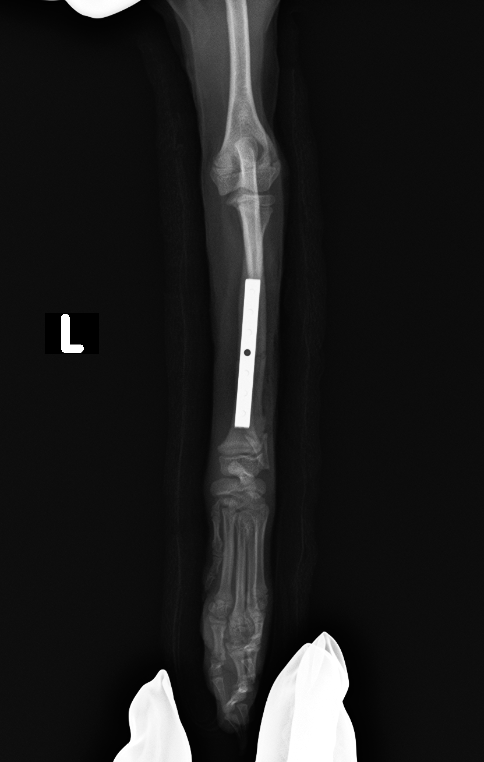

橈骨のプレート固定

after